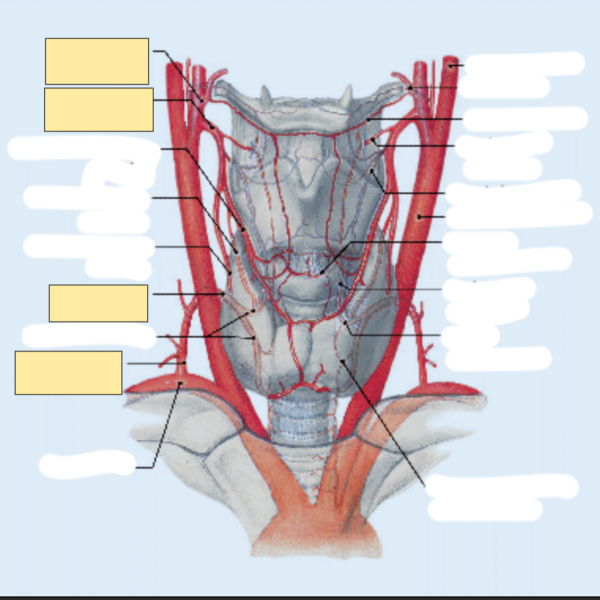

Sollte sich eine Information bildlich darstellen lassen, nutze das unbedingt! Also auch eine Abbildung der Galeazzi-Fraktur und du musst den Namen nennen. Wenn mir eine Frage nur ein Bild zeigt, ist es für mich eindeutig, dass ich das Bild benennen soll, daher nutze ich diese Struktur: {{c1::Galeazzi Fraktur::Bild}}

Bilder: Wenn du die drei Bestandteile der Galeazzi-Fraktur lernst, ist eine sehr potente bidirektionale Karte eine Abbildung der Fraktur. Siehe dazu das Beispiel im Punkt 4 Sexy.

Background:

Bidirectional:

Auch aus der Abbildung ohne Beschriftung eine Karte erstellen.